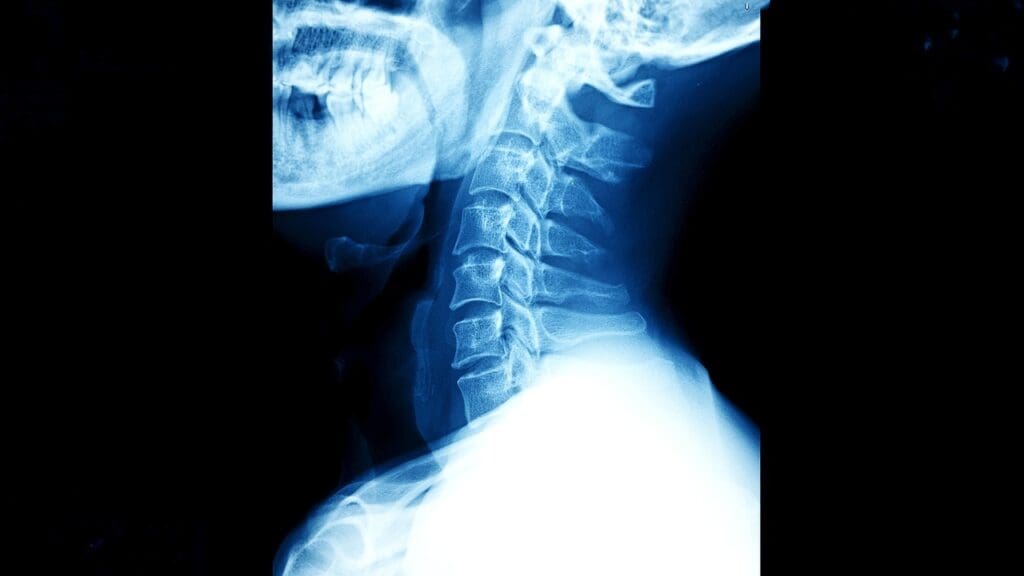

Understanding Cervical Spine Anatomy and Function

It’s key to know about the cervical spine’s anatomy and function to understand ACDF surgery. The cervical spine, or neck area, supports the head. It also allows for movement and protects the spinal cord and nerves.

Structure of the Cervical Spine

The cervical spine has seven vertebrae, from C1 to C7. Between them are intervertebral discs, which act as shock absorbers. These discs help the spine stay flexible. The vertebrae protect the spinal cord, which runs through the spinal canal.

The cervical spine’s design is special. The first two vertebrae (C1 and C2) help with head rotation. The lower vertebrae carry more of the head’s weight.